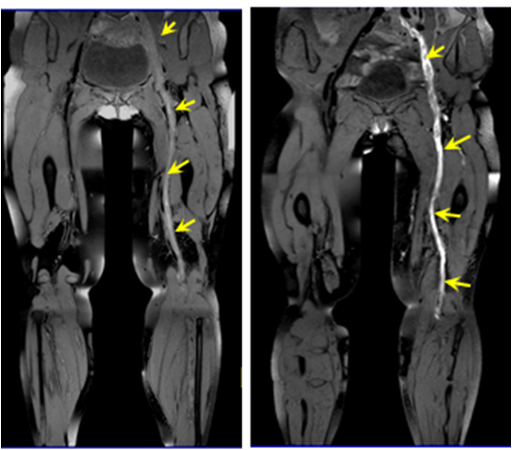

1. 本检查方案与传统静脉造影增强检查方法的成像结果比较,本方案不仅可以实现血栓分布的精准检查,还可以直接观测到血栓信号。